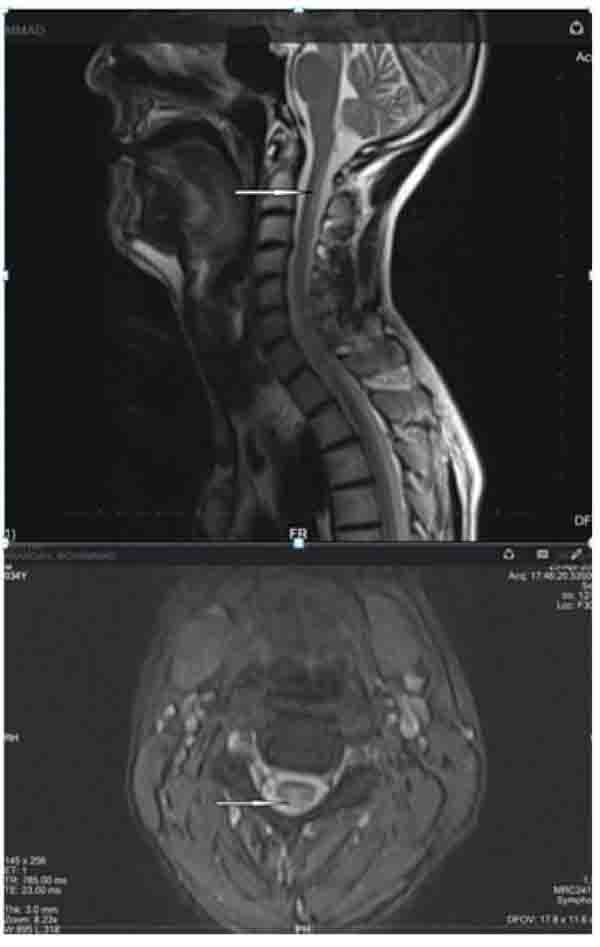

Figure 1 from Optic Neuropathy from Vitamin B12 Deficiency Associated Vitamin B12 Deficiency Optic Neuropathy The role of vitamin b12, folic acid, and copper deficiencies in nutritional optic neuropathy is well established. Vitamin b12 deficiency optic neuropathy is a rare complication of this deficiency that results in progressive, bilateral, painless vision loss that is often associated with reduced color vision and. Micronutrients known to be responsible for nutritional optic neuropathy are vitamin b12 (cobalamin), folic. Vitamin B12 Deficiency Optic Neuropathy.

Figure 2 from Optic Neuropathy from Vitamin B12 Deficiency Associated Vitamin B12 Deficiency Optic Neuropathy Optic neuropathy is a rare, but important, manifestation of vitamin b(12) deficiency that should be suspected in patients with risk factors. The role of vitamin b12, folic acid, and copper deficiencies in nutritional optic neuropathy is well established. We suggest promptly identifying and replacing vitb12 in patients with optic neuritis with proven vitb12 deficiency to prevent permanent. Micronutrients known to. Vitamin B12 Deficiency Optic Neuropathy.

Vitamin B12 deficiency optic neuropathy. (a) Fundus photographs Vitamin B12 Deficiency Optic Neuropathy First, the low serum vitamin. The role of vitamin b12, folic acid, and copper deficiencies in nutritional optic neuropathy is well established. Optic neuropathy is a rare, but important, manifestation of vitamin b(12) deficiency that should be suspected in patients with risk factors. We suggest promptly identifying and replacing vitb12 in patients with optic neuritis with proven vitb12 deficiency to. Vitamin B12 Deficiency Optic Neuropathy.